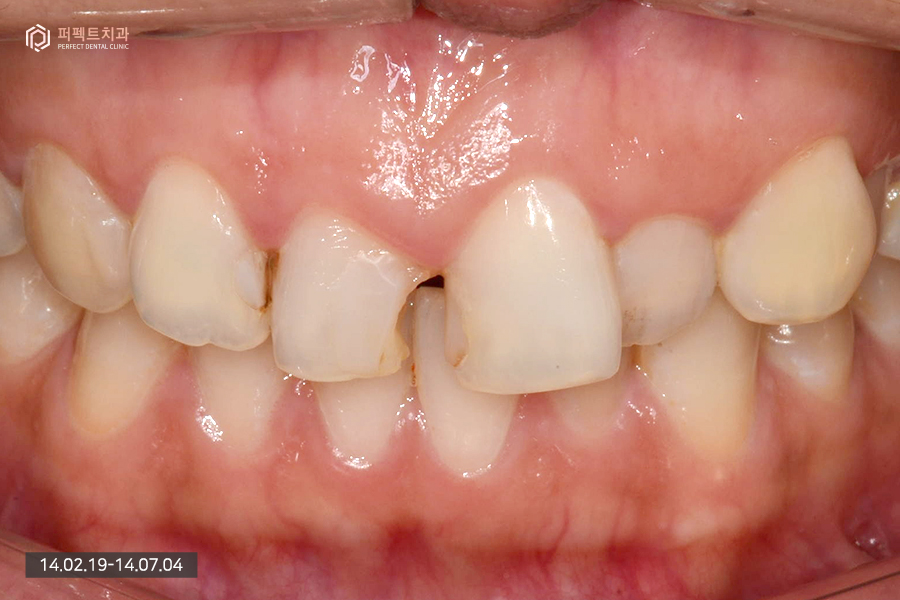

초진 사진을 보시면 앞니 사이 충치가 있는 것을 보실 수 있습니다. 예전에 앞니 충치치료를 하시면서 레진으로 때우신 상태였는데 떨어져나가고 변색, 2차 충치 등의 문제가 있던 상황이었습니다.

30대 중반의 여성분이셨는데 치열도 틀어져있고 잇몸 높이도 맞지 않는 상황이여서 치아 사이에 있는 충치는 레진치료를 하기로 하셨고 충치치료 후 3~4개월 정도 부분교정 후 치아 배열 문제를 해결하였고 그리고나서 마지막으로 라미네이트를 통해서 완성을 했습니다.

사진을 통해서 보시면 알 수 있듯이 충치가 심한 상태라 치아의 많은 부분이 없는 상태였는데 이런 경우 라미네이트를 통해서 치료를 할 수 있는지 물어보시는 분들도 계십니다.